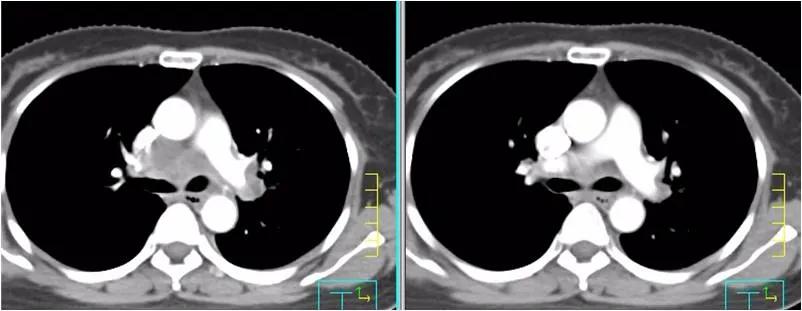

疗效评价:纵膈淋巴结及肺部转移灶均明显缩小,疗效达PR。血肿瘤指标SCC由218ng/ml下降到2.99 ng/ml。患者咳嗽、胸闷症状明显缓解。

左图为:2020-09-02治疗前 ,右图为2020-10-14两周期治疗后